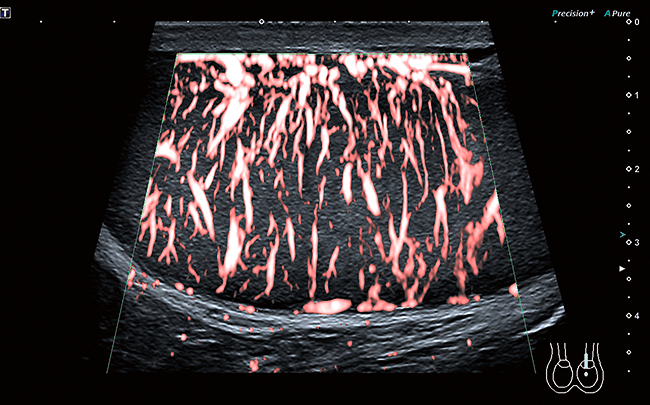

SMI G4 (Superb Microvascular Imaging): visualizzazione avanzata della microvascolarizzazione

Precision+

ApliPure+

SMI e iSMI